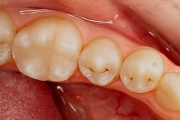

Vali sind huvitav pilt ja me näitame sellega seotud haigust ja sümptomeid